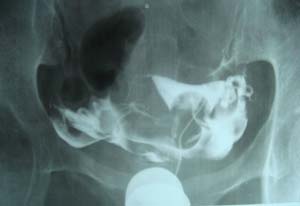

双侧输卵管是通的。

子宫输卵管造影未见明确异常。

子宫腔光整,双侧输卵管通畅,盆腔内造影剂弥散可。

各位子宫内是有个圆形充盈缺损,子宫呈倒“三角形”形态没有完全被造影剂充盈呀。子宫肌瘤。应该在拍两张斜位就好了 。

子宫体确有充盈缺损。考虑子宫肌瘤。子宫左倾

子宫输卵管造影未见明显异常,宫内充盈负影为气囊压迫所致。